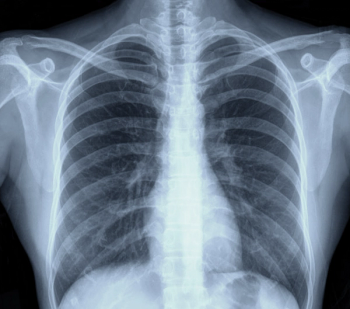

Comparing year-long findings with and without adjunctive artificial intelligence (AI) at a breast cancer screening program in Spain, researchers found the combination of digital breast tomosynthesis and AI had a 92.5 percent accuracy for diagnosing cancer in patients with elevated risk.